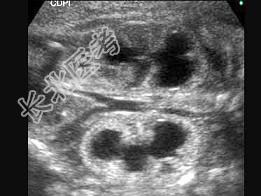

- 单项选择题图为孕34周的胎儿声像表现。根据图像特点,以下最可能的诊断为 ( )

A、肾囊肿

B、多囊肾

C、肾积水

D、肾肿瘤

E、以上都不是